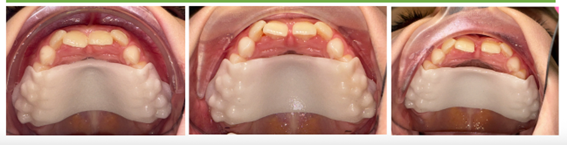

Novo Palatal Expander – Expansor Palatino Digital

O Novo Palatal Expander é uma evolução dos aparelhos expansores tradicionais. Integrado à tecnologia Invisalign e ao escaneamento digital iTero, ele permite ampliar o arco dentário de forma precisa, controlada e mais confortável para a criança.

É um expansor palatino digital que amplia o arco dentário da criança, criando espaço para o alinhamento correto dos dentes permanentes.

2. Qual a diferença para os expansores tradicionais?

Além de ser planejado digitalmente, mais confortável e discreto, não possui parafuso.

A ativação é feita trocando a placa, o que facilita muito para os pais e evita desconfortos comuns dos modelos antigos.